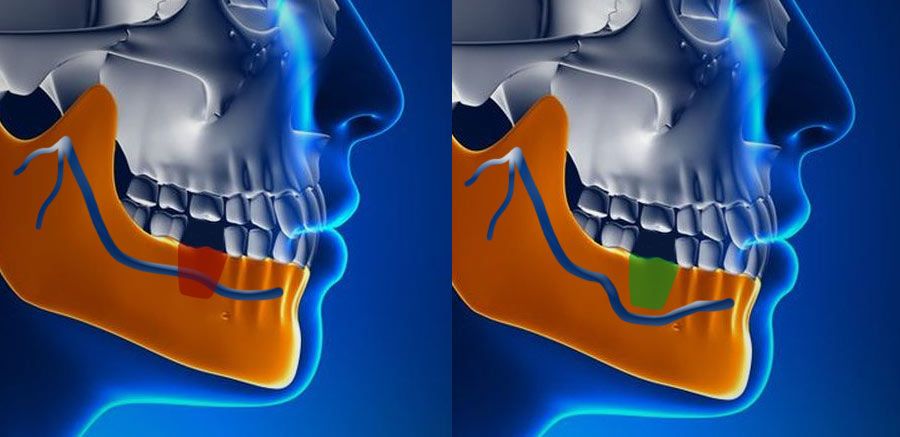

The inferior alveolar nerve, which gives feeling to the lower lip and chin, may need to be moved in order to make room for the placement of dental implants in the lower jaw. A nerve repositioning procedure is limited to the lower jaw and may be indicated when teeth are missing in the area of the two back molars and/or second premolars. This procedure is considered a very aggressive approach since there is almost always some postoperative numbness of the lower lip and jaw area, which typically dissipates very slowly, but may be permanent. Usually other, less aggressive options are considered first (placement of blade implants, etc).

Typically, we remove an outer section of the cheek on the side of the lower jaw bone in order to expose the nerve and vessel canal. We then isolate the nerve and vessel bundle in that area and slightly pull it out to the side. We then place the implants while tracking the neuro-vascular bundle. Then the bundle is released and placed back over the implants. The surgical access is refilled with bone graft material of the surgeon’s choice and the area is closed.